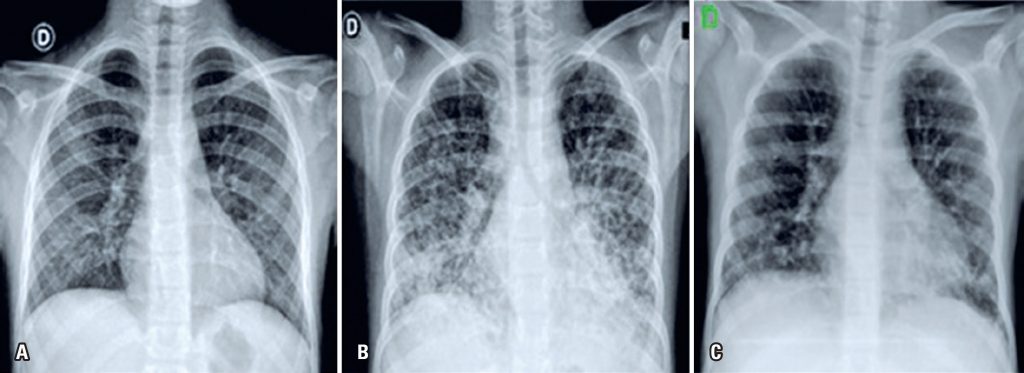

Case report of a patient with an immunodeficiency who demands regular replacement of intravenous immunoglobulin. She presented an episode of transfusion-related acute lung injury shortly after using an immunoglobulin product different than the one she usually received. The patient evolved with respiratory changes (hypoxia, dyspnea, change in pulmonary auscultation) minutes after the end of the infusion, and received non-invasive respiratory support. She was discharged after 36 hours with good outcome. The patient achieved full recovery, showing no further reactions in subsequent immunoglobulin infusions (no longer receiving the product that was used when she had the episode of transfusion-related acute lung injury). Although rare, this reaction is potentially serious and has no specific treatment other than supportive therapy. The literature is scarce regarding the risk of recurrence. The decision on whether to proceed with immunoglobulin therapy after this adverse effect should be analyzed individually, assessing the possible risks and benefits for the patient.